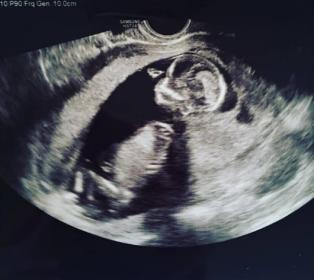

14 weeks, 2 days ultrasound - Help us guess! Please!

My daughter lost a little girl last year 20 + weeks into her pregnancy. She's pregnant now with her little rainbow baby and we're wondering if anyone can -- based on the above - hazard a guess as to what we are having? This shot was taken yesterday and I've spent hours online looking at comparisons and feel it's a boy. Just a guess based on the baby's little bottom being tilted towards the cam. But, I don't know. I can't find a photo anywhere with a baby sitting at an angle like this. LOL